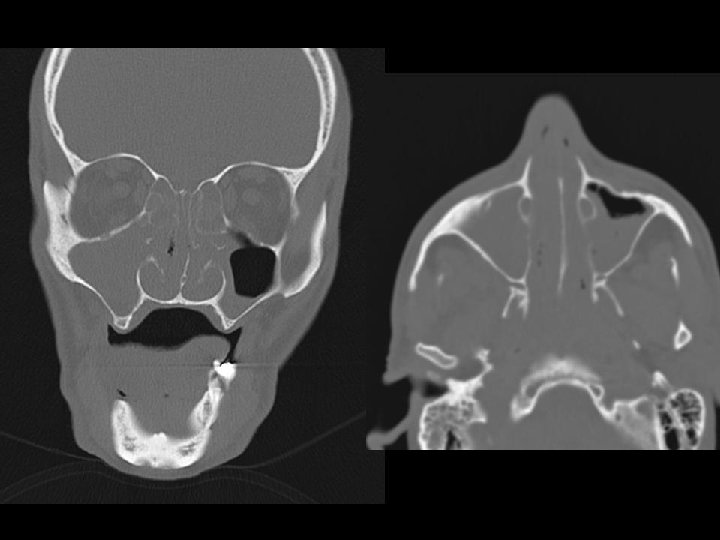

(4) Neurologist assessment: summary Initial presenting illness n Bulbar palsy with normal NCT, but clinically nil response to IVIG and steroid Deterioration right now n Cerebral dysfunction with raised CSF protein n Hypointensities in bilateral temporal and Rt BG Need to consider other diagnosis n Sinusitis with orbital + CNS extension n For contrast MRI brain + skull base

Searching for an answer, again…. . n n n n n 9 th July: Plain CT Brain (Hospital A) 7 th Aug: Plain CT Brain (Hospital A) 25 th August: Plain CT Orbit (Hospital A) 27 th August: Contrast CT brain + Sinus 4 th September: MRI brain + brainstem 4 th September: Plain CT brain 10 th September: Contrast CT brain 11 th September: Plain CT sinus 15 th September: MRI brain + DWI

Eye: no need for more OT at CMC!! We decided to reconsult ENT n ? Drainage of sinus may help sepsis control better than simply antimicrobial n ENT preferred to have procedure at CMC 12 th Sept: Lt maxillary sinus antral wash Straw colour fluid yielded Opacity “Likely mucosal oedema only” n